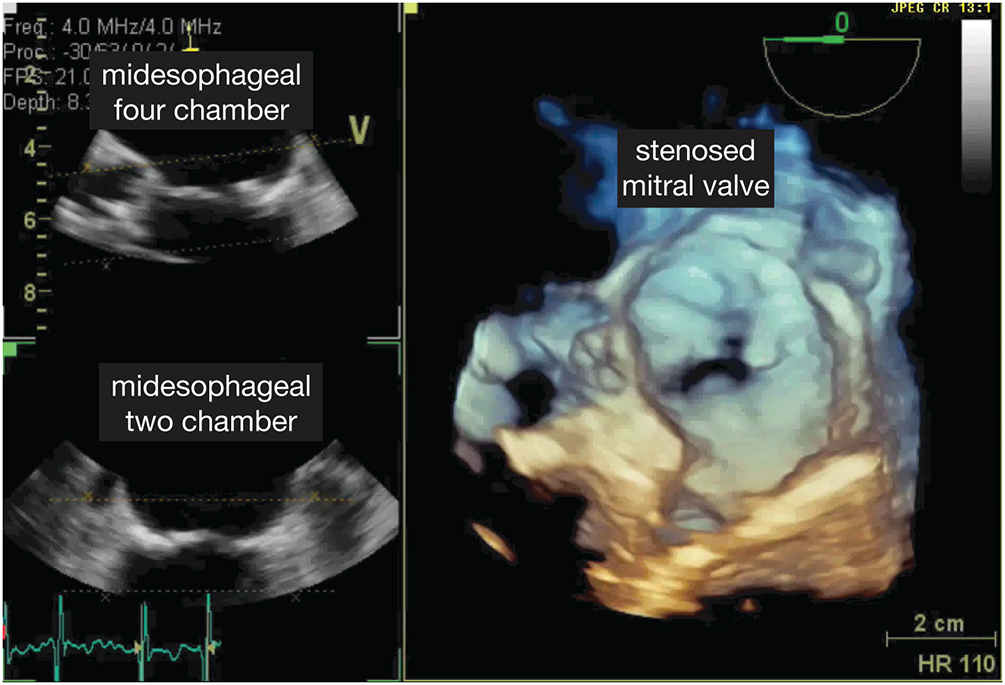

The severity of MS can be obtained by direct measurement of the diastolic gradient between the LA and ventricle at the time of cardiac catheterization. This requires a transatrial puncture, a procedure largely replaced by echocardiographic techniques. Echocardiographic diagnosis is based on gradient estimation by Doppler and by measuring the rate of decay in the pressure with the time spent in diastole (pressure halftime). The MV area (cm2) can be derived from an empirical formula wherein the MV area equals 220 divided by this pressure halftime. Severe MS is present when the mean diastolic gradient exceeds 10 mm Hg, corresponding to a valve area of less than 1.0 cm2 (Figure 7.18; Video 7.3).

Figure 7.19.: Transesophageal Echocardiographic Findings of Moderate Mitral Stenosis (Color Flow Doppler) with 3D View (Top) and 2d View (Bottom).

Transesophageal echocardiographic findings of moderate mitral stenosis (color flow Doppler) with 3D view (top) and 2D view (bottom).